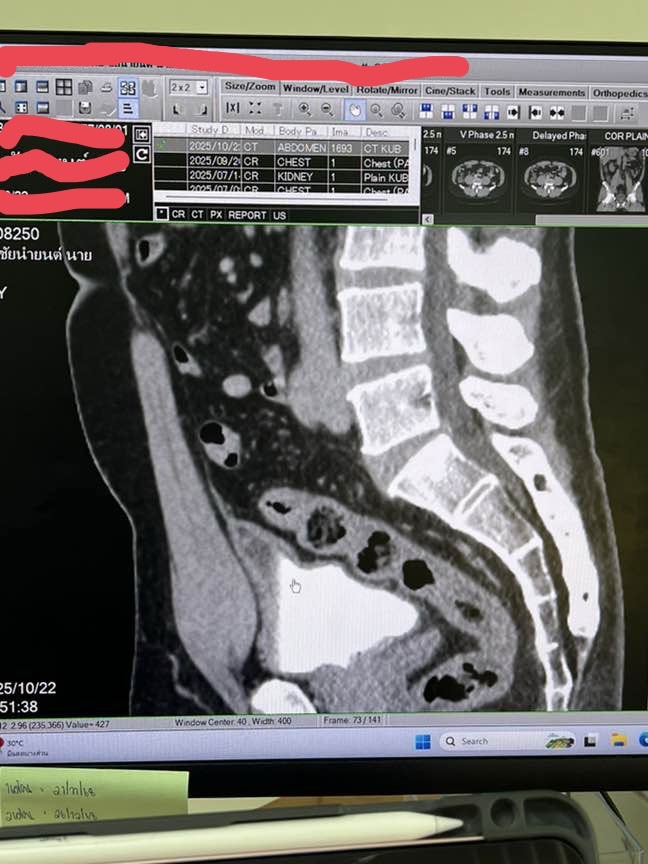

สายสะดือที่ติดกับแม่ตั้งแต่เด็ก ปัจจุบันมีเลือดผสมออกมาทางปัสสวะ ที่ตรวจเจอ 3+ ทำct scan พบสายสะดือค้างอยู่ที่ตัว แบบนี้เป็นอันตรายไหมและในรูปครับ รบกวนพี่ๆ เพื่อนๆ และคุณหมอแนะนำด้วยครับเครียดมากครับตอนนี้ ปัจจุบันอายุ 50

สุดคุณหมอนัดส่องกล้องเดือนหน้า ครับ